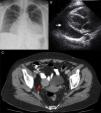

A 55-year-old woman with a history of hypertension was admitted to our institution due to severe dyspnea. On physical examination tachypnea, hypotension, and bilateral jugular distension were detected. The electrocardiogram showed sinus tachycardia. Chest radiography revealed mild bilateral pleural effusions and severe cardiomegaly (Figure 1A). An echocardiogram showed a 3-cm global pericardial effusion with signs of cardiac tamponade (Figure 1B). Due to the patient's clinical instability, drainage of the pericardial effusion was mandatory, but pericardiocentesis was unsuccessful due to catheter obstruction, and so surgical drainage was performed through a pleuropericardial window. Cytology and pericardial biopsy detected no malignant cells. Abdominal computed tomography showed ascites and a 3 cm × 4 cm ovarian fibroma (Figure 1C). Given the benign nature of the tumor, an expectant attitude was adopted.

A: Anteroposterior chest X-ray showing mild bilateral pleural effusion and massive bottle-shaped heart manifesting severe cardiomegaly; B: Two-dimensional echocardiography showing a 3-cm global pericardial effusion (arrow) and signs of cardiac tamponade; C: Pelvic computed tomography showing a right ovarian tumor, a fibroma (arrow).